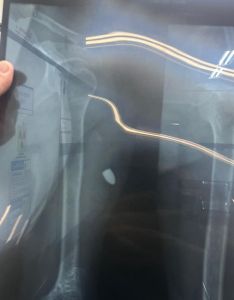

A vítima sentiu um forte impacto no ombro esquerdo, mas não entendeu de imediato o que estava acontecendo.

O socorro foi acionado após colegas notarem que estava saindo sangue. Ela foi encaminhada para o Hospital João XXIII. O projétil, calibre .38, foi retirado e a vítima recebeu alta.